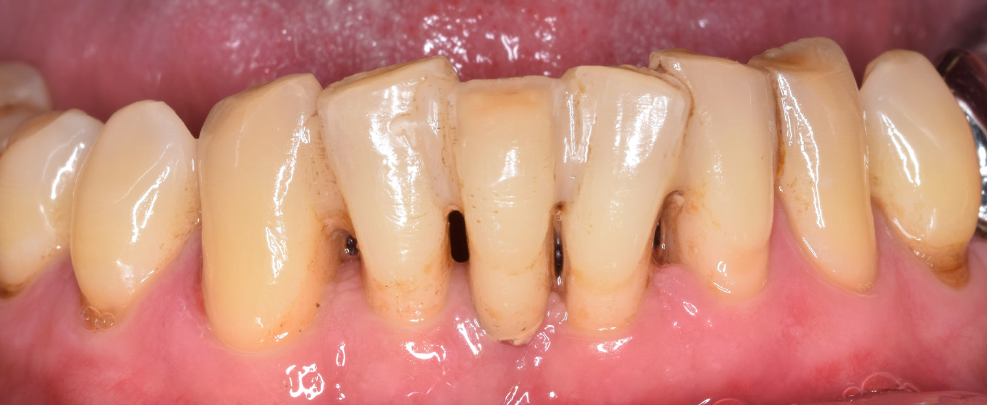

Boala parodontală este una dintre cele mai întâlnite patologii de la nivelul cavității bucale și unul din principalii factori cauzali pentru pierderea dinților. Debutul și evoluția ei sunt insidioase, de multe ori durerile și sângerările gingivale apărând doar în fazele avansate ale bolii. Acest lucru duce și la prezentarea tardivă a pacienților și îngreunarea tratamentului. Prevenția este cea mai bună armă de apărare împotriva distrucției parodontale avansate. Retracția gingivală și resorbția osoasă sunt cele mai evidente simptome care duc pacienții la căutarea unui tratament conservator. Cu toate că există soluții multiple de tratament, există și situații când singura indicație validă este extracția dentară. Dinții afectați de boala parodontală primesc indicații de extracție atunci când suportul osos remanent nu mai poate menține dintele pe poziția lui inițială. Pierzându-se os pe toată circumferința dinților, aceștia devin mobili (se mișcă). O anumită mobilitate fiziologică este prezentă și la nivelul dinților naturali, dar mobilitatea dinților parodontotici este mult crescută.

Una din soluțiile adjuvante în terapia bolii parodontale o reprezintă imobilizarea dinților, care este o metodă de fixare rigidă, unind mai mulți dinți cu ajutorul unor sisteme speciale care pot fi executate în laboratorul de tehnică dentară (metalice) sau aplicate direct în cabinetul de medicină dentară. Cele mai folosite sunt cele care au la bază o bandă din fibră de sticlă fixată adeziv pe suprafața dinților.

Când se pierd sau se extrag dinți din zona estetică (frontală), există anumite situații când acești dinți pot fi fixați în sistemul de imobilizare în scop estetic, pe termen scurt-mediu. (Fig. 5.4.1 și Fig. 5.4.2)